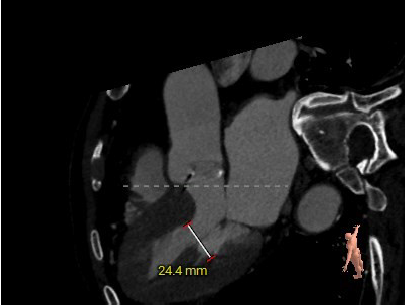

患者为71岁高龄男性,患者因反复胸闷15年,再发2月,5月慕名自行前来我院就诊。主动脉瓣听诊可闻及粗糙、高音调的喷射性收缩期杂音,余无特殊。术前超声显示瓣环直径28mm,左房37mm,左室收缩末内径55mm,左室流出道24mm。窦管高度17mm,内径39mm。瓣上最大流速3.7m/s,峰值压差56mmHg,平均压差34mmHg。诊断为主动脉瓣重度狭窄伴轻度关闭不全,二尖瓣轻中度反流。

主动脉根部评估:

左冠高度12.5mm右冠高度18.4mm,右冠脉开口高度大于瓣叶长度,SOV瓦式窦:平均周长径39.0mm,术中仍球囊预扩须密切注意冠脉灌注,STJ周长径39.2mm。

瓣叶重度钙化伴增厚,钙化分布不均匀,HU750积分1048mm²。